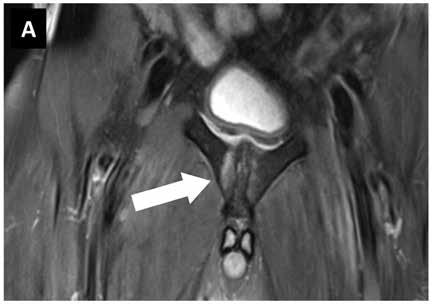

Um ein Knochenmarködem festzustellen, muss eine Magnetresonanztomografie (MRT) durchgeführt werden. Diese Flüssigkeitsansammlung unter der Knochenhaut verursacht starke Schmerzen, die auch ohne Belastung des betroffenen Bereichs anhalten können.